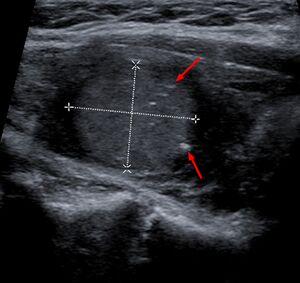

يتم التشخيص بشكل أساسي عن طريق الشفط بالإبرة الدقيقة لآفة الغدة الدرقية لتمييزها عن الأنواع الأخرى من آفات الغدة الدرقية.[6] سيظهر الفحص المجهري سدى نشواني مع تضخم في الخلايا المجاورة للجريب.